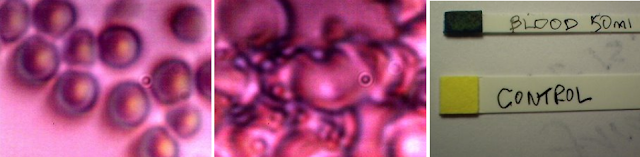

Di seguito sono presentate alcune immagini rappresentative per promuovere la curiosità. Rappresentano alcuni dei risultati imprevisti della sperimentazione culturale dell'epoca, insieme ai successivi test dell'emoglobina che hanno avuto luogo. All'epoca le apparecchiature per microscopi erano relativamente giovani nello sviluppo, ma tutto il lavoro è distintivo, unico e ripetibile fino al punto di necessità. Il secondo documento mostra significativi miglioramenti della qualità con apparecchiature e tecniche di microscopia. I lettori dovrebbero anche prestare attenzione all'inconfondibile presenza del CDB nei campioni di sangue esaminati o in coltura, anche da oltre 10 anni.

![]() |

| Lavoro di cultura e test dell'emoglobina dal documento "Blood Issues Intensify", aprile 2009. Ingrandimento ca. 3000X. |

| Unico lavoro di coltura eritrocitaria (sangue) e CBD dell'Istituto Carnicom nel 2009. Ingrandimento ca. 8000 - 10000x. |